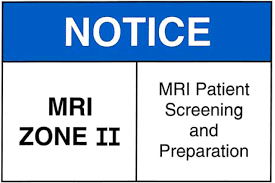

MRI Zone 2

Zone 2: Patient Screening and Prep